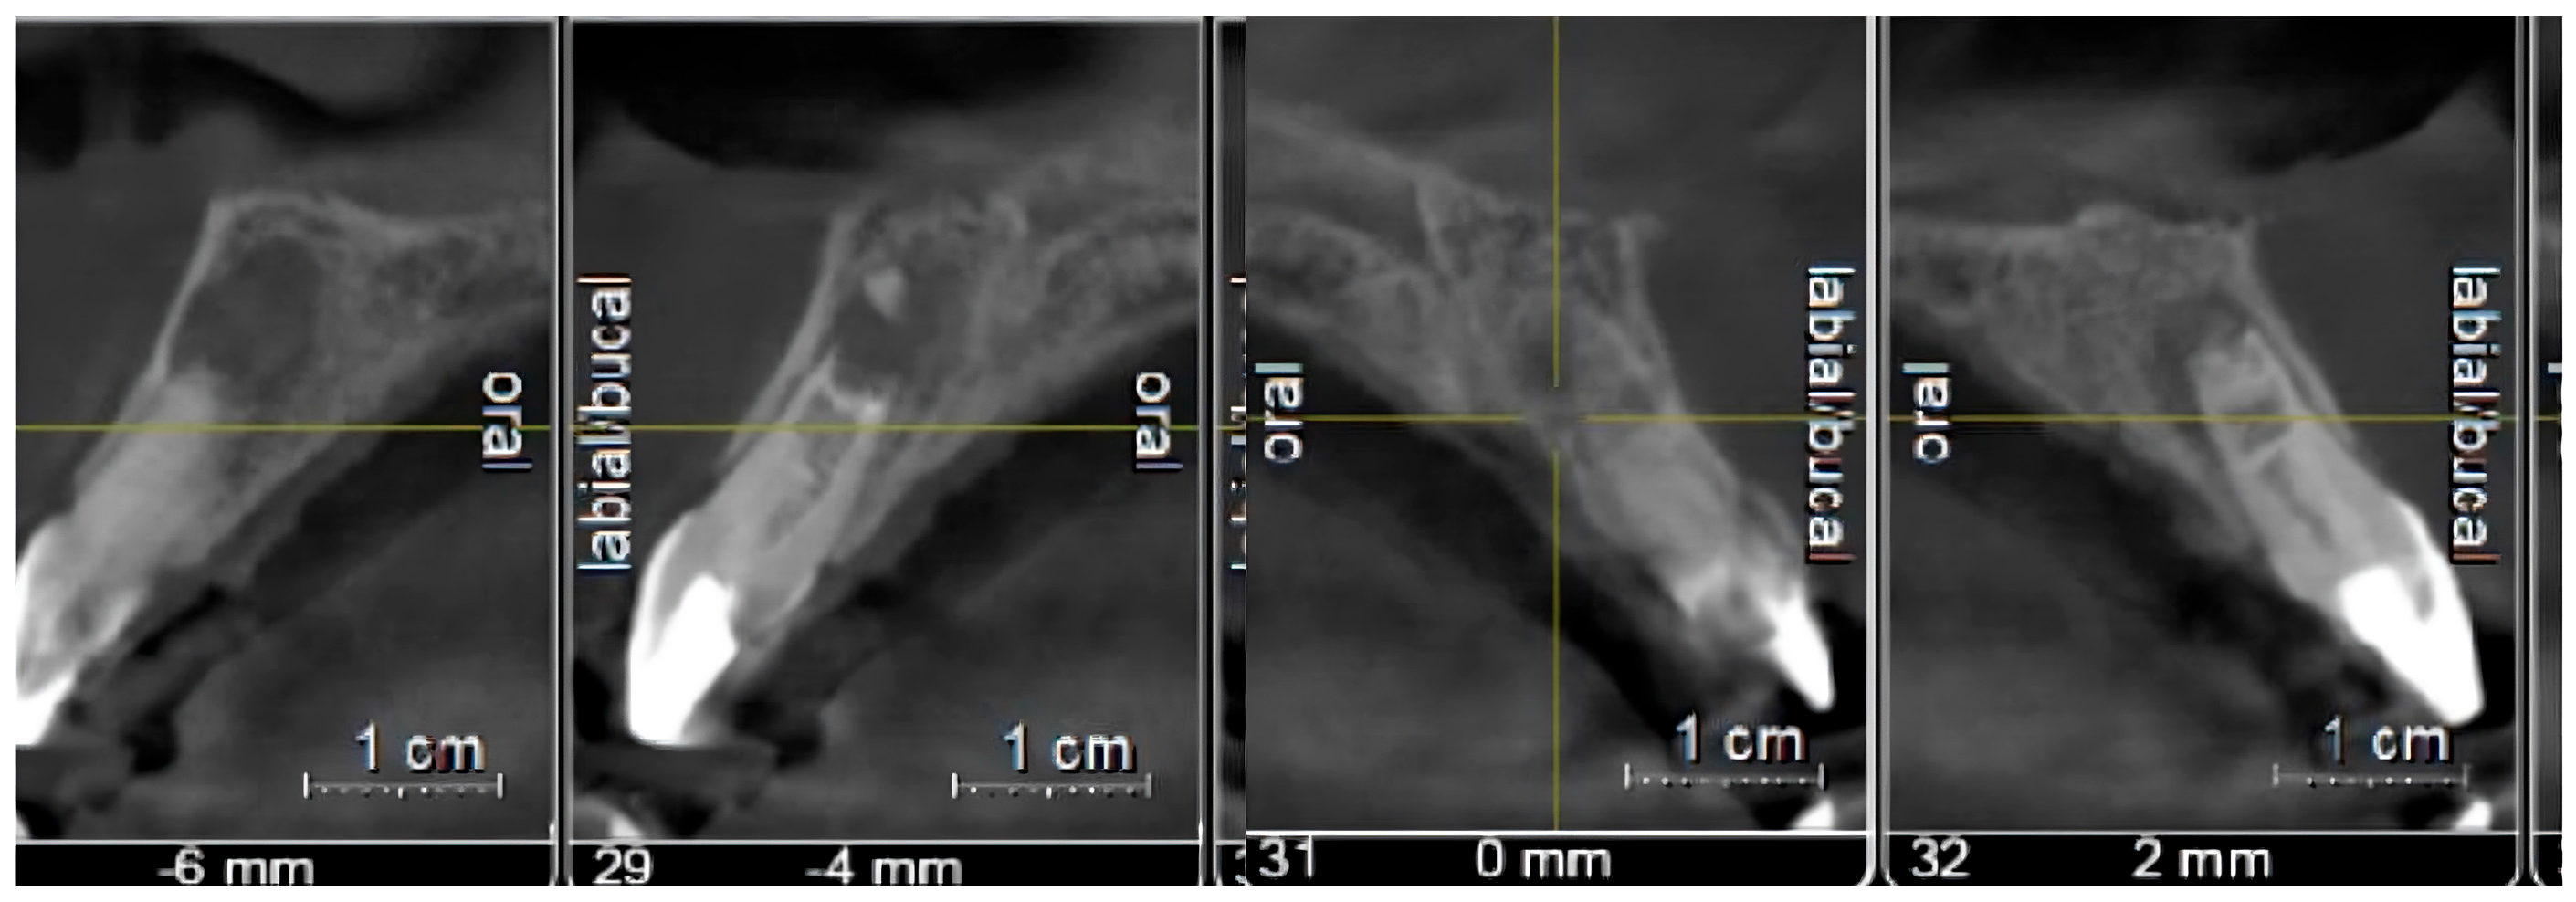

| Case 1 | 12 | 17% EDTA NaOCl | TAP | MTA | 3.7 mm | 2.2 mm | Calcified apical barrier |

| Case 2 | 11/21 | 17% EDTA NaOCl | Ca(OH)2 | BIODENTINE® | 3.1 mm/2.8 mm | 2.3 mm/2 mm | Calcified apical barrier |